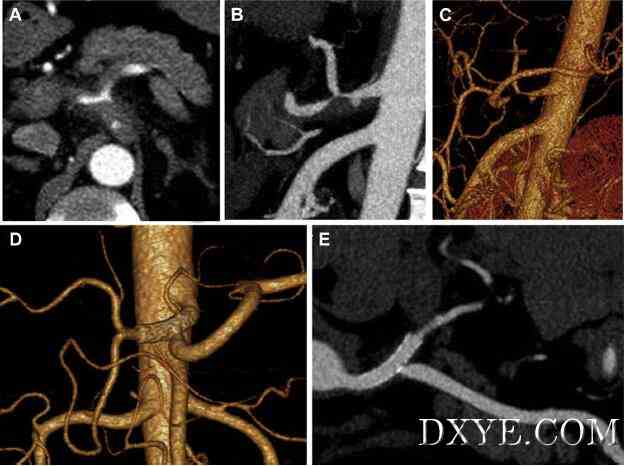

形态学发现和治疗的腹腔动脉(SIDCA)自发隔离夹层。在本回顾性研究中纳入2009年1月至2014年12月期间23例SIDCA患者。回顾了这些患者的人口统计学数据,临床特征,形态学结果,治疗方式和随访结果。我们提出了类似于肠系膜上动脉自发隔离解剖的SIDCA的形态学分类。 腹腔动脉自发性分离解剖形态学分类(SIDCA)。 I型,假腔同时进入和再入; II型,“死路”型假腔无再次进入; III型,具有溃疡样突起(ULP)的血栓性假腔; IV型,完全血栓形假腔,无ULP; 和V型,与解剖相关的动脉瘤发展。 保守治疗的IIIa型患者。 A,初始计算机断层扫描(CT); B,CT 6个月后; 和C,CT后12个月。 一个IIIb期患者血管内治疗。 A-C,解剖涉及腹腔干,脾动脉和肝动脉。 真腔几乎完全闭塞。 D和E,假腔消失,支架和分支在裸支架植入腹腔干和肝动脉。 结果在最初,11例患者接受血管内治疗,12例接受医疗治疗。四个医疗治疗患者的解剖出现加重,需要血管内抢救。所有患者均成功恢复。没有的患者出现腹痛,需要再次手术,或死亡。在医学治疗组中,假腔在4名患者中完全血栓形成并被吸收,部分血栓形成在2处。所有支架均获得专利,假腔完全血栓形成并在血管内组中被吸收。 该研究得出,SIDCA可以在稳定的患者中进行医学治疗,但需要密集随访。血管内治疗可应用于具有复发性症状,内脏灌注不足或动脉瘤的高危患者。如果血管内修复不合适或失败,应考虑开放手术。血管内管理的短期结果令人鼓舞,但需要进行长期随访的进一步评估。 |